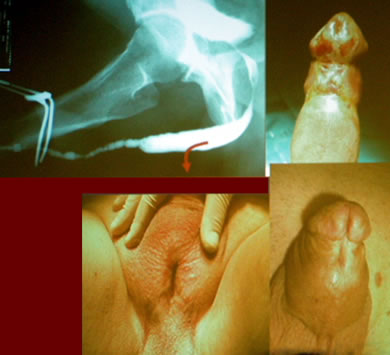

"Новые технологии в лечении стриктур уретры"